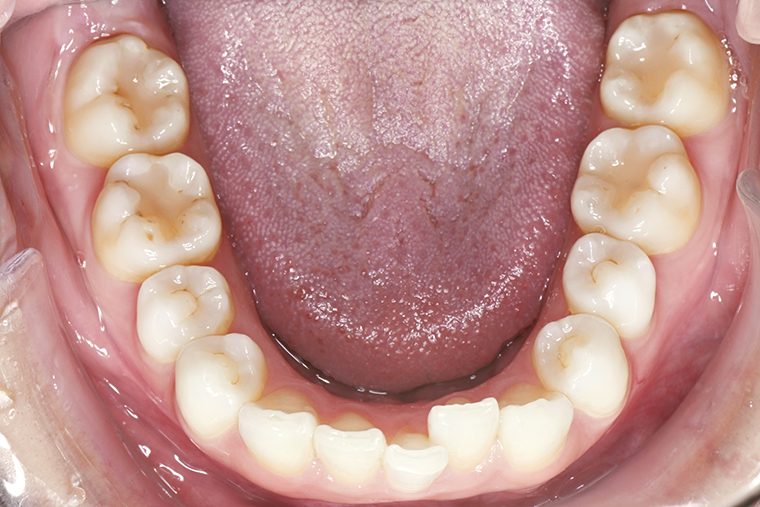

Case Study29歳女性ガタガタな歯のマウスピース矯正-矯正期間1年(2023年11月開始)